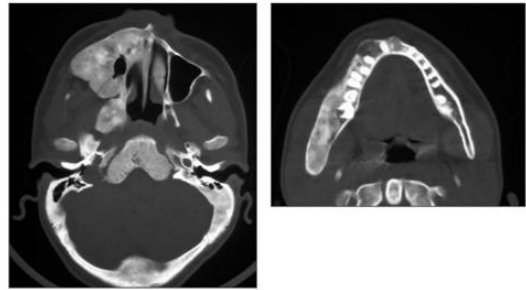

68.一位12歲女孩,顏面無痛腫脹已有3年,其電腦斷層影像如圖,她的皮膚上還有咖啡牛奶 斑。其最可能的診斷是:

(A)Florid-osseous dysplasia (B)McCune-Albright's syndrome (C)Paget's disease (D)von Recklinghausen disease of skin